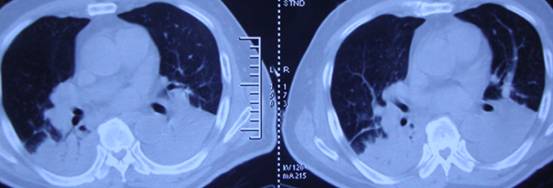

某患者男性,73岁,因间断性上腹部胀痛1个月入我院,于2012年12月14日全麻下行胃癌根治性全胃切除术,12月19日因出现呼吸困难转入ICU科。入科查体:体温39.0℃,脉搏120次/分,呼吸42次/分,血压102/80mmHg,外周血氧饱和度(FiO2 60%)84%,口唇及四肢指端发绀。听诊双下肺呼吸音减弱,少许湿?音,心界不大,心率 120次/分,律整。腹带包扎,左、右各留置腹腔引流管一枚接引流袋,空肠营养管1枚,腹部压痛,无明显反跳痛及肌紧张。四肢无水肿。辅助检查:(入科急检)动脉血气分析(FiO2 60%):PH7.40,PaO2 65 mmHg,PaCO2 35mmHg,BE -2.5mmol/L。胸腹部CT检查:双肺下叶及右肺上叶后段可见肺组织实变。腹部CT:腹腔内可见水样密度影。

胸部影像 双肺斑片状模糊影 双下肺实变

四天后患者体温降至37℃,脱离呼吸机,呼吸频率降至18次/分,复查血气分析氧合指数恢复正常,复查肺部CT(2012-12-24治疗后),示右肺实变明显好转,左肺实变较前减轻,肺膨胀度明显改善,患者病情好转转出ICU病房。